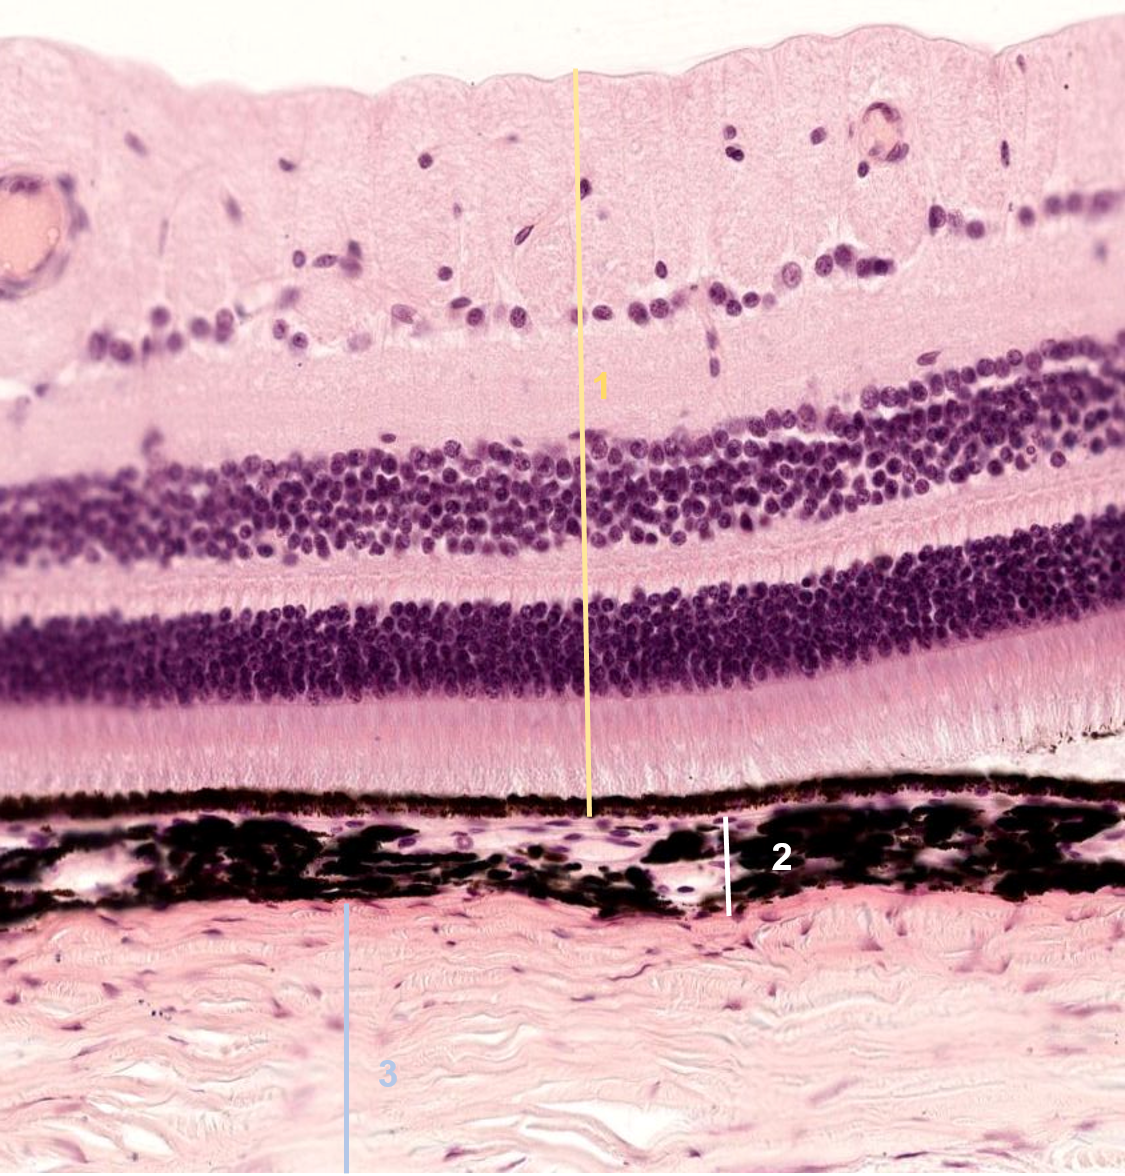

1: Retina

2: Coroide

3: Esclerótica